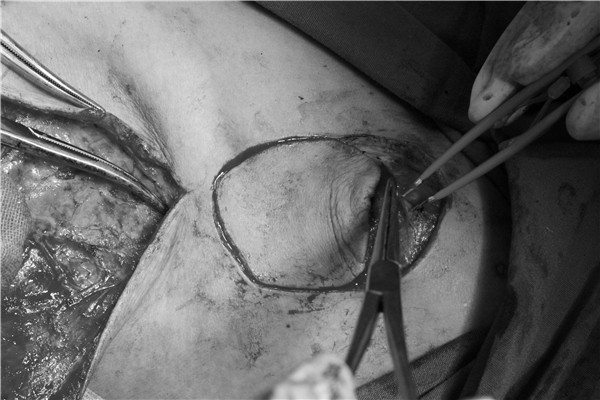

近日西安交大二院耳鼻咽喉头颈外科病院连续为多例病人采用锁骨上动脉岛状瓣成功修复下咽癌术后组织缺损。术中根据下咽缺损部位和范围设计不同形状大小的血管轴形皮瓣,精细解剖裸化血管,结合微创咽瘘切口,细致缝合获良好功能恢复。这是我院继开展内镜下环后、咽后壁癌等离子刀切除,免气管切开声门旁间隙入路梨状窝癌切除后,针对晚期下咽癌外科治疗的又一技术进步。

患者周先生,男,49岁,下咽恶性肿瘤。检查发现该肿瘤位于右侧梨状窝,累及杓会皱襞,传统手术一般采用全喉切除,术后患者将失去正常的呼吸、吞咽和发音功能,对生活质量影响巨大。能否在完全切除肿瘤的同时最大限度地保留或修复喉功能成为治疗小组面临的难题。患者入院后,任晓勇主任、王正辉主任医师、许映龙主治医师组成的手术小组和肿瘤放化疗医师、影像科医师等一起进行了MDT讨论,一致认为:患者年轻,保喉愿望强烈,而肿瘤虽然侵犯杓会皱襞,但声带运动尚可,切瘤保喉有可行性。肿瘤范围较大,涉及下咽外侧及后壁,可经下咽侧壁切开切除肿瘤,但咽瘘面积大,须采用皮瓣修复,术后辅以放化疗,能够获得喉功能保全的满意效果。手术小组随后对皮瓣的选择进行了专门讨论,决定采用锁骨上动脉岛状瓣,这是近年新兴的一种组织修复技术。该皮瓣松软薄,表皮细腻,血供丰富,距离缺损组织距离合适,灵活性高,同时对放射线耐受性好。4月16日在任晓勇主任的指导下,王正辉主任医师、许映龙主治医师、陈佳文医师在麻醉科、手术室的大力配合下,显微解剖裸化颈横动脉-锁骨上动脉血管轴,顺利修复喉及下咽的组织缺损,术后喉镜检查皮瓣色泽完全正常,喉功能恢复理想,术后7天出院。